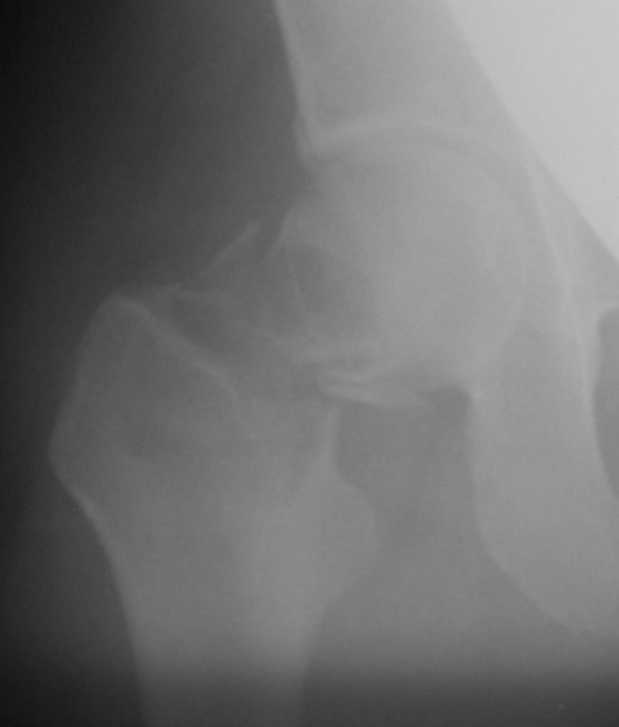

Приношу извинения, думал, что на прилагающейся рентгенограмме видно, что перелом произошел на месте обширной кисты, занимающей шейку и вертельную область. По характеру перелом многооскольчатый, дуга Адамса также представлена в виде осколков.

"Поправил" рентгенограмму. Так не лучше?